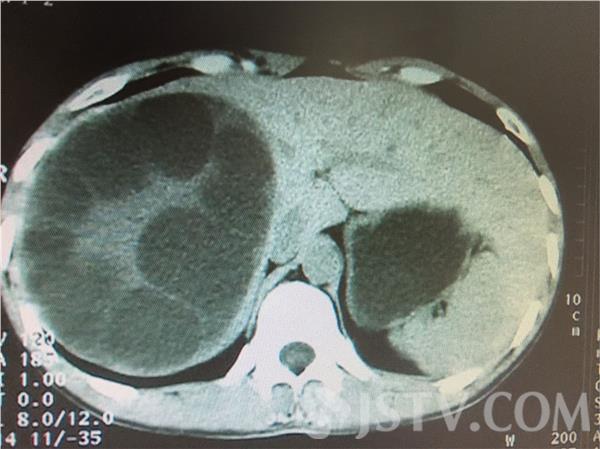

肝包虫病主要流行于畜牧业发达地区,在江南一带极为罕见。最近,南通一名女子被查出有肝包虫囊肿,手术切出来的肝包虫竟有2公斤重。

昨天,记者在医院见到了手术后的母女士,她术后恢复良好。32岁的母女士祖籍云南,10多年前来到南通。一个月前,她突然感到右上腹胀痛不适。医院通过CT检查,发现导致母女士腹部膨胀的原因是肝右叶上的巨大肿瘤,推断是患上了肝包虫囊肿。这种病主要流行于畜牧业发达地区,在江苏极为罕见,可能与母女士的饮食卫生习惯有关。

近日,医院为母女士成功实施了肝包虫囊肿切除术。专家介绍,发病的主要地区在牧区,牧区牛羊狗这些动物比较多,一旦饮食不注意,生食以后虫卵就进入到我们体内,然后随着门静脉系统进入到肝脏,在肝脏形成肝包囊肿。